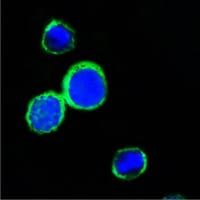

分类: 科研抗体货号: 20352别名: RPS27应用: IF反应种属: Human